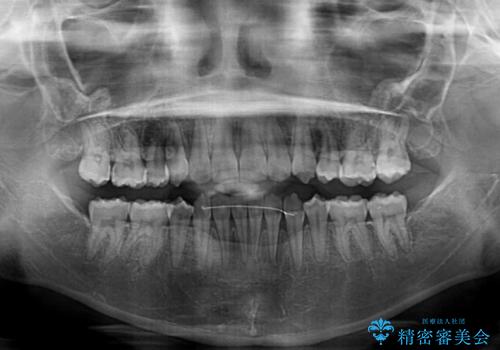

- 顕著な八重歯が気になるとのことで来院された患者様です。

インビザラインでの治療を希望されましたが、インビザライン単独では困難と判断されたため、補助装置や一部ワイヤー装置を用いて行うこととしました。

叢生が強いため、上下左右第一小臼歯4本を抜歯することとしました。

ワイヤー装置を用いた場合、一般的には2年程度で終了することを考えると、「移動量が多くなると治療期間が長くなる」というインビザライン矯正の最大の弱点が現れた治療となりました。